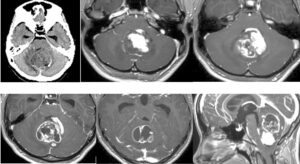

外頸動脈から腫瘍濃染が認められていたため、ある程度の出血は予想して手術に入りましたがそれ以上でした。内減圧が出血でなかなか進みません。腫瘍を硬膜から剥がすと主要表面からも動脈性出血が起こり、止血に難渋しました。腫瘍表面を凝固操作しているうちに、手術の最終段階で顔面神経はしっかり確認できるが電気的反応がなくなりました。手術が長時間かかった関係で小脳が挫傷となって腫れてしまい、救命のため小脳を一部切除してようやく手術を終えることができました。術後、小脳失調、顔面神経麻痺が出現し、術後1週間程度は意識も悪かったです。幸い術後3週間目から急速に回復され、食事や補助歩行が可能となりました。顔面神経のENoGの反応も残っており、回復が期待できます。現在リハビリ中です。これまで最大級の難敵でしたが、無事に生還してよかったです。